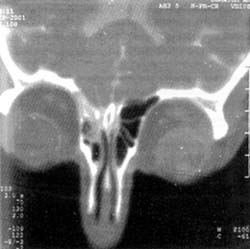

Η ασθενής υπεβλήθη σε CT δεξαμενογραφία, με έγχυση μετριζαμίδης κατά τη διάρκεια της οποίας ελήφθησαν μετωπιαίες τομές μόνο, λόγω του ότι η ασθενής δεν μπορούσε να ανεχθεί τομές σε στεφανιαίο επίπεδο. Η εξέταση απεκάλυψε παρουσία της σκιαγραφικής ουσίας στις πρόσθιες ηθμοειδείς κυψέλες (εικόνα 1) ενδεικτικό εκροής (διαφυγής) Ε.Ν.Υ. από το παρακείμενο τμήμα του τετρημένου πετάλου του ηθμοειδούς οστού.

Εικόνα 1